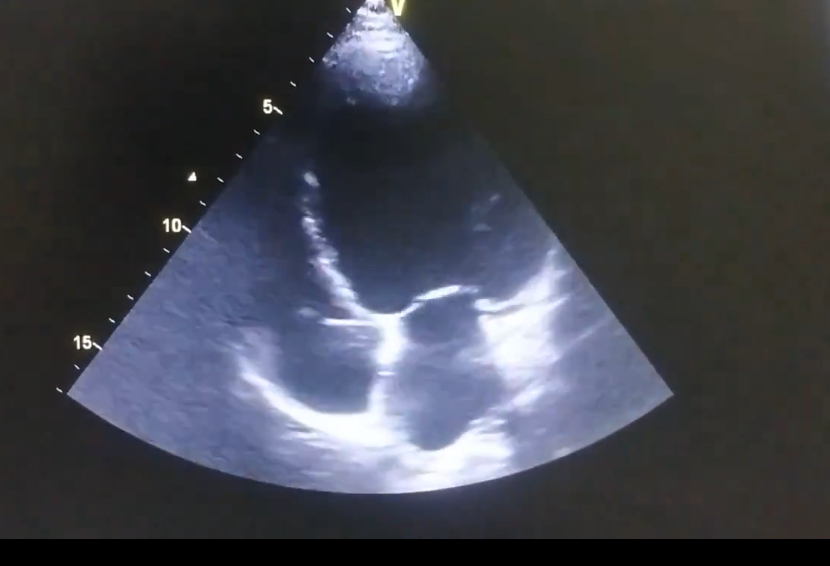

Abstract Body (Do not enter title and authors here): Darier’s disease (DD) is a rare autosomal dominant dermatologic disorder caused by mutations in the ATP2A2 gene, which encodes the sarco/endoplasmic reticulum Ca2+-ATPase pump (SERCA2). While DD is classically characterized by hyperkeratotic papules, nail changes, and mucosal involvement, ATP2A2 is also abundantly expressed in cardiac myocytes, where SERCA2a plays a central role in calcium handling and myocardial contractility. I present a unique case of dilated cardiomyopathy (DCM) in a 22-year-old male with longstanding, biopsy-confirmed DD. The patient developed progressive exertional dyspnea, orthopnea, and declining functional capacity. Dermatologic examination showed discrete hyperkeratotic papules in flexural areas and longitudinal erythronychia with distal splitting of fingernails. Echocardiography revealed global hypokinesis, dilated cardiac chambers, and a reduced left ventricular ejection fraction of 28%. Extensive evaluation excluded ischemic, infectious, autoimmune, and metabolic causes. Genetic testing identified a pathogenic heterozygous ATP2A2 mutation. Given the known cardiac expression of SERCA2a, a mechanistic link between the patient’s cutaneous and cardiac phenotypes was strongly considered. To my knowledge, this represents one of the few documented cases highlighting a potential association between DD and cardiomyopathy. This case expands the phenotypic spectrum of ATP2A2 mutations and underscores the need to consider cardiac screening in symptomatic DD patients. Recognition of such systemic associations is essential for early diagnosis, personalized care, and appropriate multidisciplinary management. Further investigation into the cardiovascular manifestations of ATP2A2-related disorders is warranted.